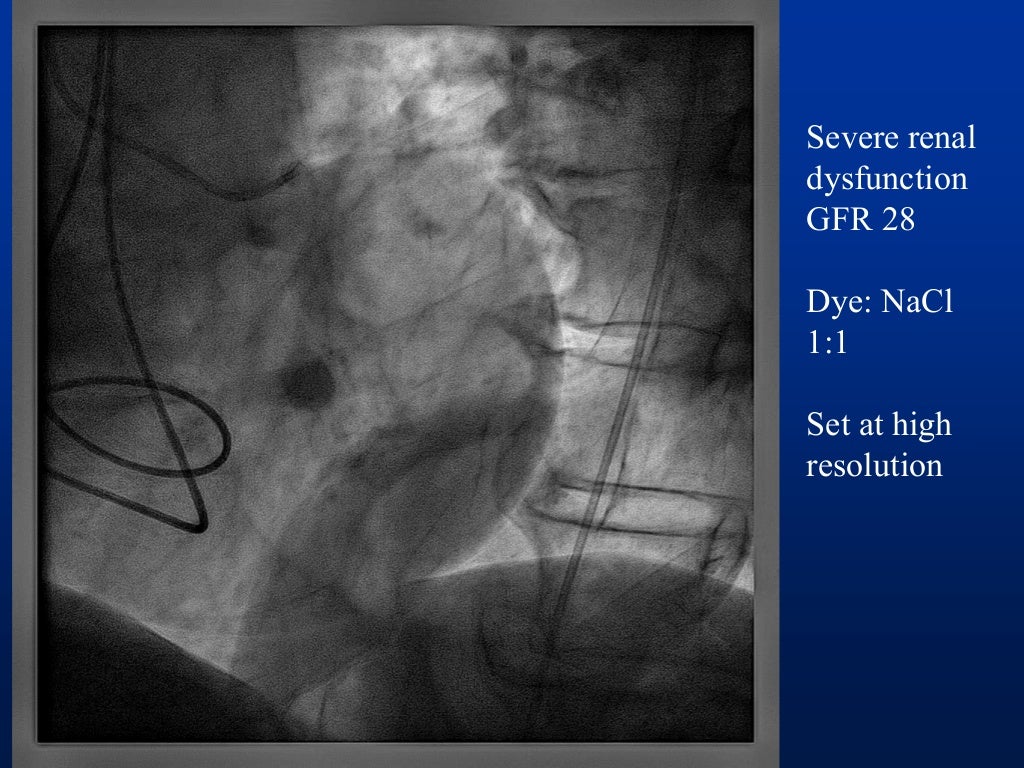

I) use collimator to set minimal useful field size, keep image intensifier in close proximity.

This principle confers to physicians the responsibility for reducing as much as possible the dose of radiation during cardiovascular procedures to minimize the. Radiation exposure can be accumulated over the time of. We strive to perform only tests that are necessary and to use just enough radiation doses to provide a high quality image to help your.

There are various types of shielding used in the reduction of radiation exposure including lead aprons, mobile lead shields, lead glasses, and lead barriers. The purpose of this article is to (a) describe the importance of educating radiology personnel, patients, and referring clinicians about the concerns over ct radiation, (b). Every diagnostic medical procedure involving ionizing radiation needs to minimize radiation exposure without compromising the benefit for the patient.